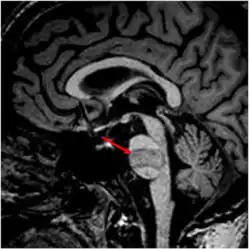

Причиной развития синдрома является поражение в области моста мозга или среднего мозга[1]. Поражение этой области может развиваться вследствие инфаркта мозга, кровоизлияния в мозг, нервно-мышечных и демиелинизирующих заболеваний (Например: центральный понтинный миелинолиз), травмы[6], опухоли[7], инфекционного поражения.[8][9]

Самой частой причиной является ишемический инсульт и кровоизлияние в ствол мозга[5][10][11], травма головного мозга (непосредственное повреждение в области ствола мозга или вторичное из-за повреждения или тромбоза базилярной артерии, кровоснабжающей эту область, а также нарастающего отека головного мозга)[12][13], реже встречается синдром запертого человека вызванный нервно-мышечными заболеваниями (Например: Синдром Гийена-Барре[14], поздние стадии бокового амиотрофического склероза[15][16]), лекарственными препаратами и ядами[17][18]. Инфекции, как причина синдрома запертого человека встречаются крайне редко[19][20]. На фоне пандемии Covid-19 стали появляться сообщения, о случаях развития синдрома как осложнения коронавирусной инфекции (как вследствие тромбоза сосудов из-за повышенной склонности к тромбообразованию[21], так и в следствии тяжелого нервно-мышечного поражения)[22].

Наиболее часто при синдроме запертого человека происходит повреждение ствола мозга в области передних отделов моста или среднего мозга. В этом регионе проходят: кортикоспинальный тракт иннервирующий мышцы конечностей, кортико-бульбарный путь к ядрам черепных нервов (тройничный нерв, лицевой нерв, языко-глоточный, блуждающий, добавочный и подъязычный нервы). Этим объясняется наличие в клинической картине паралича конечностей (поражение кортико-спинального пути), нарушение речи и глотания и мимики (поражение путей к черепным нервам). При этом пути проходящие в задних отделах остаются неповрежденными, так при сохранности ядер и путей глазодвигательного нерва возможны движения глаз по вертикали, также не нарушается слух. Ретикулярная формация, благодаря которой сохраняется сознание проходит в более задних отделах и не страдает. На основании сохранности тех или иных структур, создана классификация синдрома запертого человека.[23][8]

• МРТ человека с инфарктом головного мозга в области моста мозга (указан стрелкой), вследствие тромбоза базилярной артерии, у которого развился синдром запертого человека.